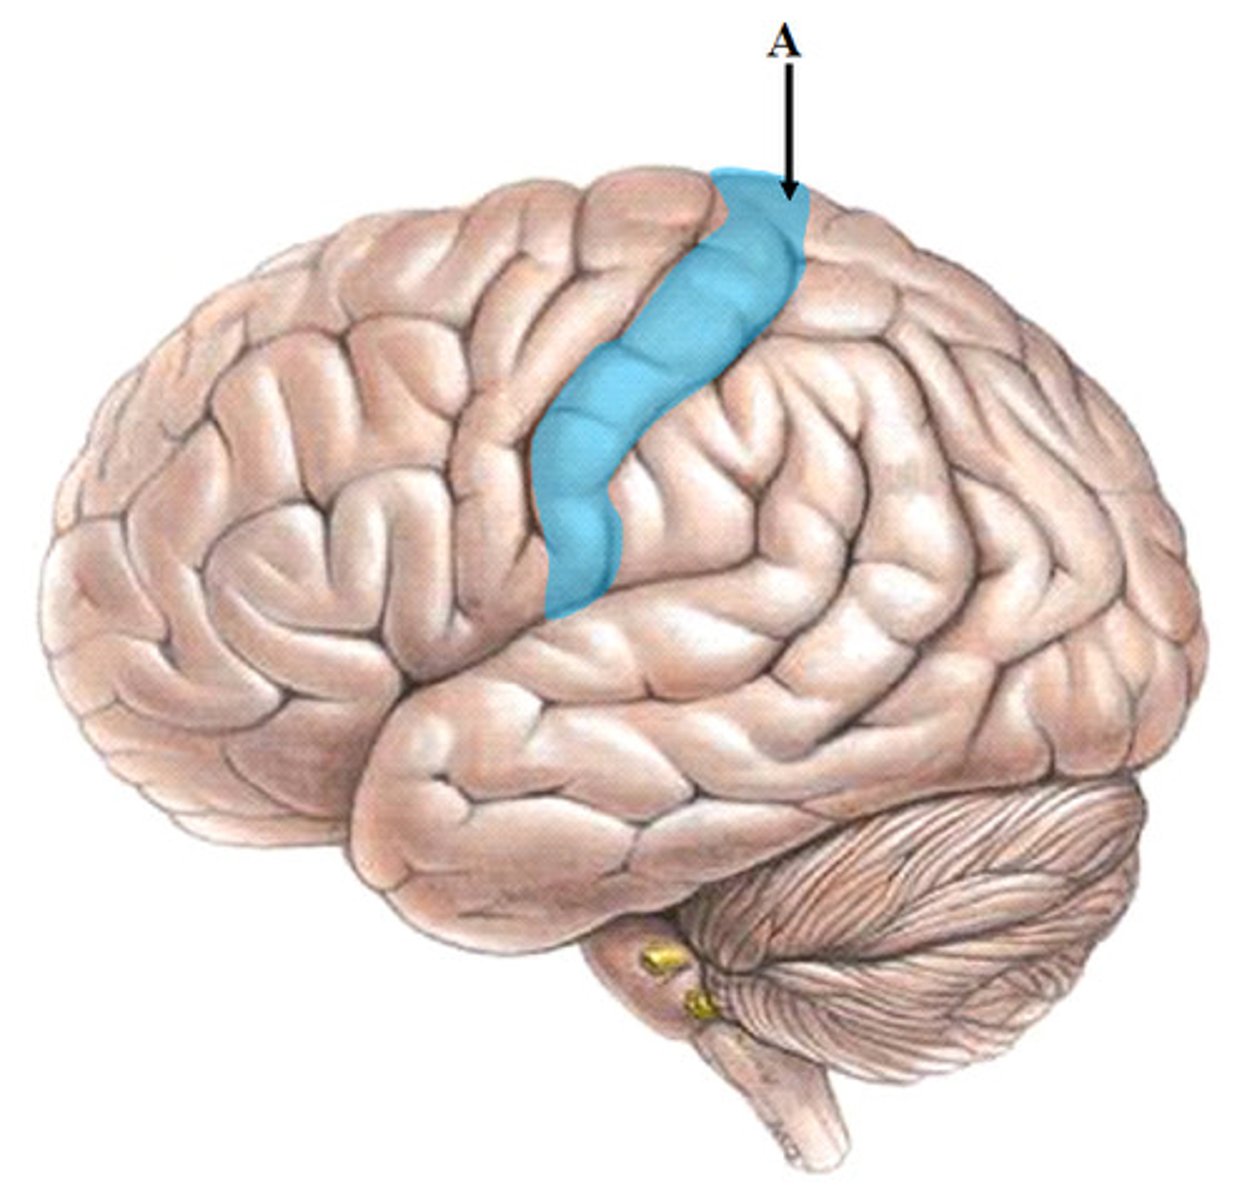

precentral gyrus

primary motor cortex

central sulcus

between postcentral and precentral gyri

frontal lobe

associated with social cues, personality, planning, movement, emotions, and problem solving - contains primary motor cortex

parietal lobe

A region of the cerebral cortex whose functions include processing information about touch, contains primary somatosensory cortex